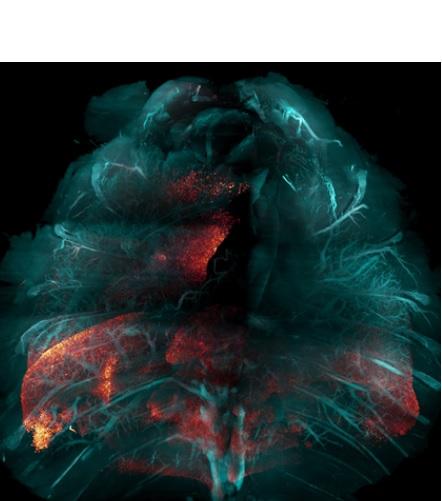

Cette nouvelle technique d’une équipe du Scripps Research (La Jolla) qui permet de rendre les tissus humains (et animaux) transparents, va faciliter considérablement l’étude de nombreuses maladies, à l'échelle du corps et telles que l'infection COVID-19. La méthode, présentée dans la revue Nature Methods, consiste à « nettoyer » les tissus afin de rendre transparents de grands échantillons biologiques. La technique permet ainsi aux scientifiques de visualiser et d'étudier plus facilement les processus biologiques sous-jacents de multiples systèmes et organes, sains ou malades.

Cette nouvelle technique, nommée « Hybrid » combine des éléments de 2 approches existantes de nettoyage des tissus, avec l’objectif de pouvoir étudier de grands échantillons. L’auteur principal, Li Ye, professeur de neurosciences au Scripps Research ajoute que la méthode permet l’étude de « grands systèmes du corps ou même d'animaux entiers ».

Le nettoyage des tissus implique l'utilisation de solvants pour éliminer les molécules qui rendent les tissus opaques (comme la graisse). L’objectif est de rendre les tissus optiquement transparents, tout en maintenant en place et en préservant la plupart des protéines et des structures. Les scientifiques utilisent couramment des balises fluorescentes codées génétiquement ou liées à des anticorps pour marquer des gènes actifs ou d'autres molécules d'intérêt chez un animal modèle de laboratoire, et les balises peuvent ensuite être « imagées » en une seule fois pour l'ensemble de l'animal.

La nouvelle méthode utilise une combinaison séquentielle de solvants organiques et de détergents à base d'eau ainsi que des hydrogels qui permettent de protéger les molécules du tissu qui doivent être préservées. La procédure est simplifiée : « Dans de nombreux cas, il est possible de mettre le tout dans un bocal et le conserver dans un shaker sur votre paillasse jusqu'à l’analyse », explique Victoria Nudell, co-auteur et chercheur au Scrpps. « Il devient possible d’effectuer l’analyse en routine ».

Preuve de concept et application au COVID-19 : La preuve de concept est ici apportée avec toute une série d’expériences, dont la capture, pour la première fois des cellules infectées par le SRAS-CoV-2 dans l'ensemble des poumons d’une souris. Les chercheurs travaillent également au traçage des voies nerveuses dans tout le corps.